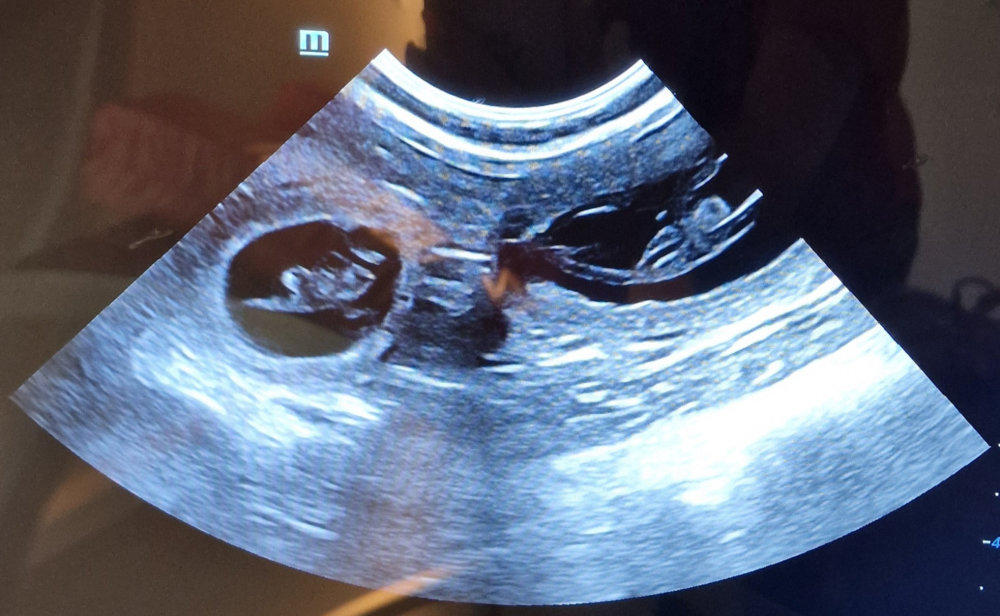

Unser Frauli war mit Enja und Yule „Babys gucken“. Smile.

Enja links. Ein bisschen „Kopfkino“ hat unser Frauli ja schon, denn der Zwerg unten links liegt „mega doof“, um das mal vor- sichtig auszudrücken. So ähnlich war es bei Lotta auch. Jetzt müssen wir alle Daumen und Pfötchen drücken, damit das Baby diese absolut unbequeme Position noch aufgibt und sich richtig hindreht. Ein paar Tage haben wir ja noch.

Bei Yule, logischer- weise rechts, ist alles „chic“!!!